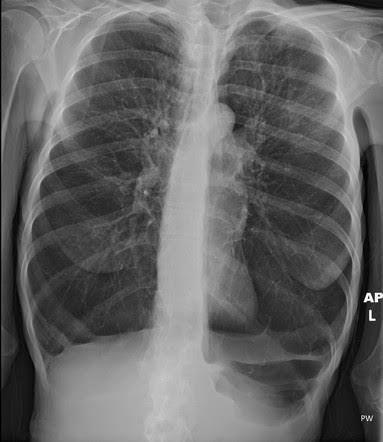

People who have emphysema are also more likely to develop: Collapsed lung (pneumothorax). A collapsed lung can be life-threatening in people who have severe emphysema, because the function of their lungs is already so compromised. This is uncommon but serious when it occurs. Heart problems. Emphysema can increase the pressure in the arteries that connect the heart and lungs. This can cause a condition called cor pulmonale, in which a section of the heart expands and weakens. Large holes in the lungs (bullae). Some people with emphysema develop empty spaces in the lungs called bullae. They can be as large as half the lung. In addition to reducing the amount of space available for the lung to expand, giant bullae can increase your risk of pneumothorax